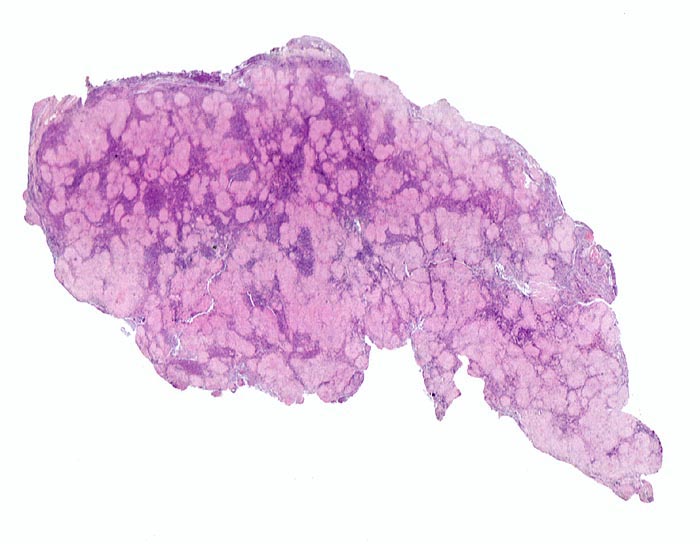

Sarkoidose des Lymphknotens

Lymphknoten, inguinal

• Wenig erhaltenes Lymphknotengewebe (blau).

• Konfluierende Granulome aus grossleibigen Epitheloidzellen.

• Wenige mehrkernige Riesenzellen.

• Kleinere Nekroseareale im Zentrum grösserer Granulome. (Die Nekrosen sind untypisch für die Sarkoidose, können aber bei grossen Granulomen gelegentlich vorkommen).

• Perigranulomatöse Fibrose. Das sollte der Kliniker dem Pathologen mitteilen:

Sarkoidosegranulome bestehen aus Epitheloidzellen mit einem peripheren Lymphozytensaum. Mehrkernige Riesenzellen, meistens solche vom Langhans-Typ mit hufeisenförmig angeordneten Kernen und Asteroidkörperchen (> 4173) können zusätzlich vorhanden sein. Diese Granulome enthalten meist keine Nekroseherde (=produktives Granulom). Man findet diesen Granulomtyp hauptsächlich in Lymphknoten, aber auch in inneren Organen und in der Haut. Die Sarkoidosegranulome zeigen in späteren Stadien eine charakteristische perigranulomatöse und die Granulome septierend unterteilende Fibrose (> 4015).